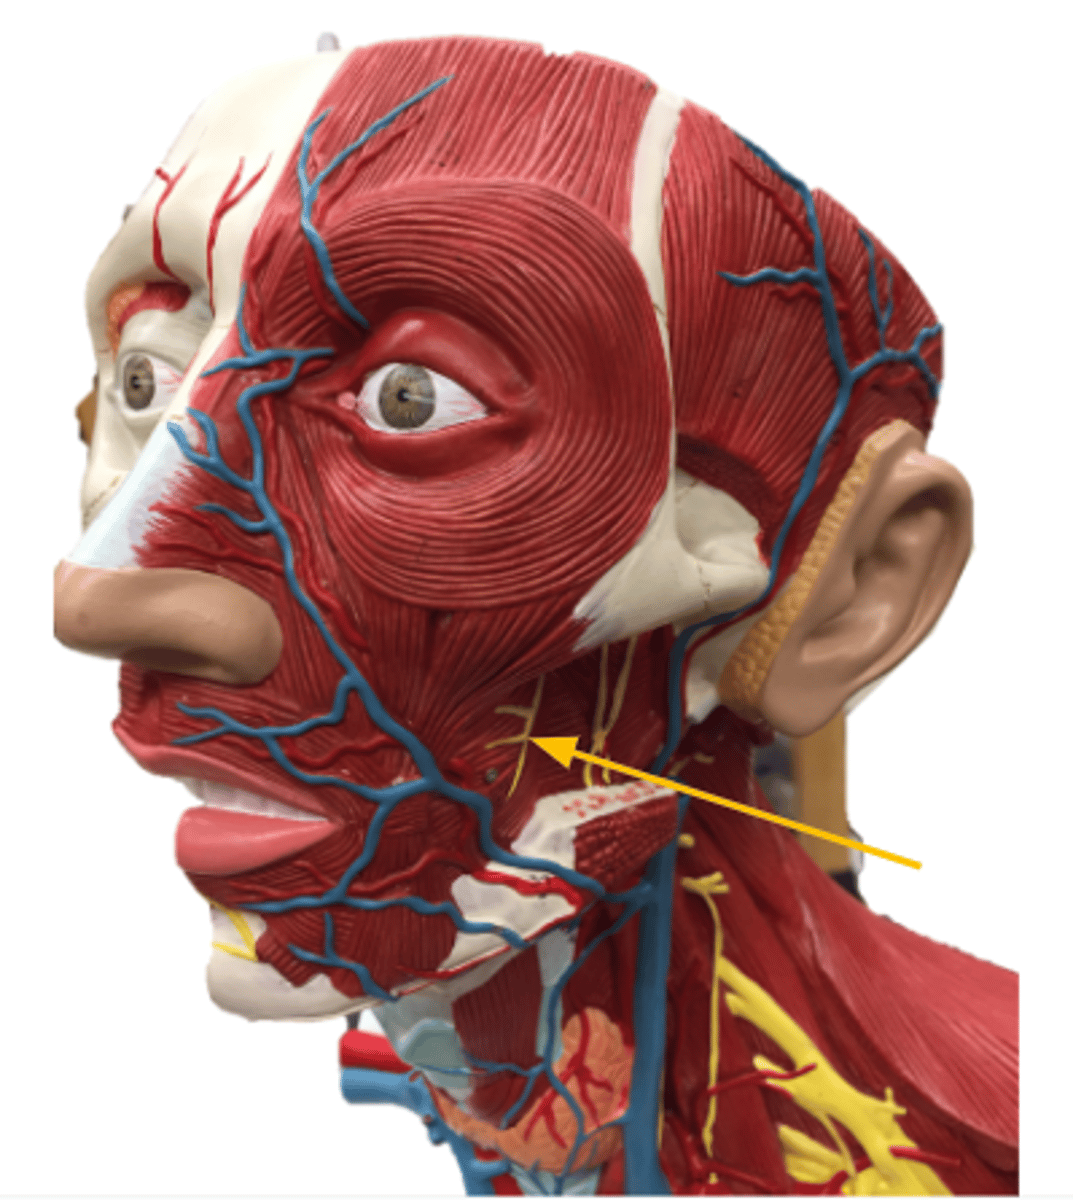

facial nerve